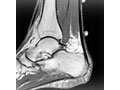

- MRI scan. It may be used to check the tendon for signs of tendinopathy or a tendon tear. An MRI is also used to evaluate the heel bone.